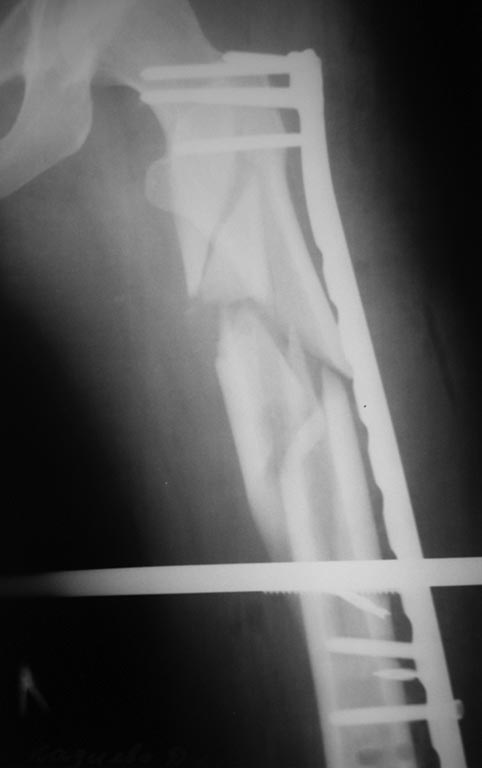

Пациентка К., 23 л., красивая девушка, уроженка одного из удаленных южных регионов России. Травма 31.12.13 в результате ДТП (столкновение а/машин). Находилась на лечении в нашем травматологическом отделении со следующим диагнозом: Сочетанная травма: ОЧМТ: Ушиб головного мозга легкой степени. Перелом передней стенки лобной пазухи со смещением отломков. Перелом латеральной стенки левой орбиты без смещения отломков. Ушибленные раны левого верхнего века. Ушиб левого легкого. Закрытое вертикально-нестабильное повреждение таза: трансфораминальный перелом крестца слева, частичный разрыв левого крестцово-подвздошного сочленения, вертикальный оскольчатый перелом крыла левой подвздошной кости со смещением отломков, поперечный перелом левой вертлужной впадины без смещения отломков. Закрытый многооскольчатый перелом левой бедренной кости в в/3 и с/3 со смещением отломков. Травматический шок II ст.

При поступлении (снимок): АВФ типа "передняя рама" на кости таза с блоком на бедренную кость,

дальнейшее лечение проходило у нас. Кости таза фиксированы канюлированными винтами и АВФ. Предполагался БИОС бедренной кости, однако из-за отсутствия в больнице современных имплантов

(угадайте с 3-х раз- почему?)и средств у больной был выполнен 22.01.14 малоинвазивный остеосинтез проксимального отдела бедра чем Бог послал (каким-то чудом оказавшаяся у нас дистальная бедренная пластина "Деост", не б/у) (см. снимки)-критика принимается. П/операционный период гладкий. Выписана с рекомендацией начать нагрузку на конечность через 12 недель после операции. Убыла на малую родину. Дальнейшая связь поддерживалась по e-mail. Рекомендации она не соблюдала: нагрузку на ногу начала недели 3 назад. Сейчас беспокоят боли в одноименном коленном суставе, отека нет, болей в месте перелома нет, анализы в норме, незначительное ограничение движений в ТБС. По месту жительства выполнила КТ (снимки и описание в приложении). Местные коллеги утверждают, что необходимо сделать реостеосинтез, но сами не берутся. Вопрос больше от пациентки: "Делать ли повторную операцию сейчас, или некоторое время походить с полной нагрузкой и сделать контроль, а там решать?"